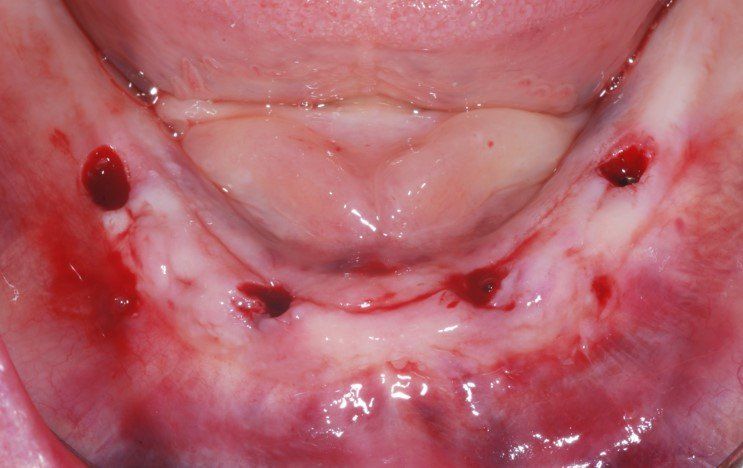

Il risultato alla fine della chirurgia di implantologia dentale è quello che si evidenzia nella foto: nessuna ferita ampia, nessun punto di sutura, inserimento ideale degli impianti secondo la guida del computer, spesso effettuato immediatamente.

Altri vantaggi che potrai avere con questa tecnica sono la durata dell’intervento, ridotto a un terzo del tempo rispetto alla chirurgia tradizionale, ma soprattutto un comfort postoperatorio notevolissimo: gonfiore e dolore quasi inesistenti o comunque controllabili facilmente con i farmaci. Insomma è questo il futuro prossimo, o meglio la piacevole realtà presente dell’implantologia dentale.